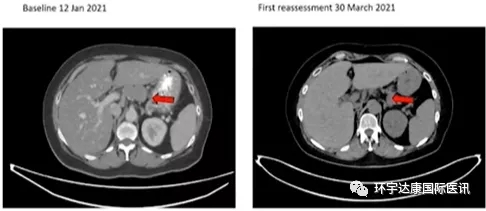

2021年9月13日,美国Adaptimmune Therapeutics公司再次传来喜讯,宣布其新型TCR-T疗法ADP-A2M4CD8 细胞疗法在多个实体瘤中进行的 1 期 SURPASS 试验的最新数据显示,该疗法具有抗肿瘤活性,这项数据将在9 月 16日ESMO 大会上正式公布。

在代号为 SURPASS 的1 期试验中,共招募了25位晚期转移性癌症患者,并且这些患者平均接受了3种治疗方案,可以说是临床上很难治疗的患者。截止到2021年8月2日,这些患者都接受了ADP-A2M4CD8细胞疗法,最终22名患者可评估。

2.一名卵巢癌患者报告了完全缓解,并且输注后 6 个月仍在持续缓解;